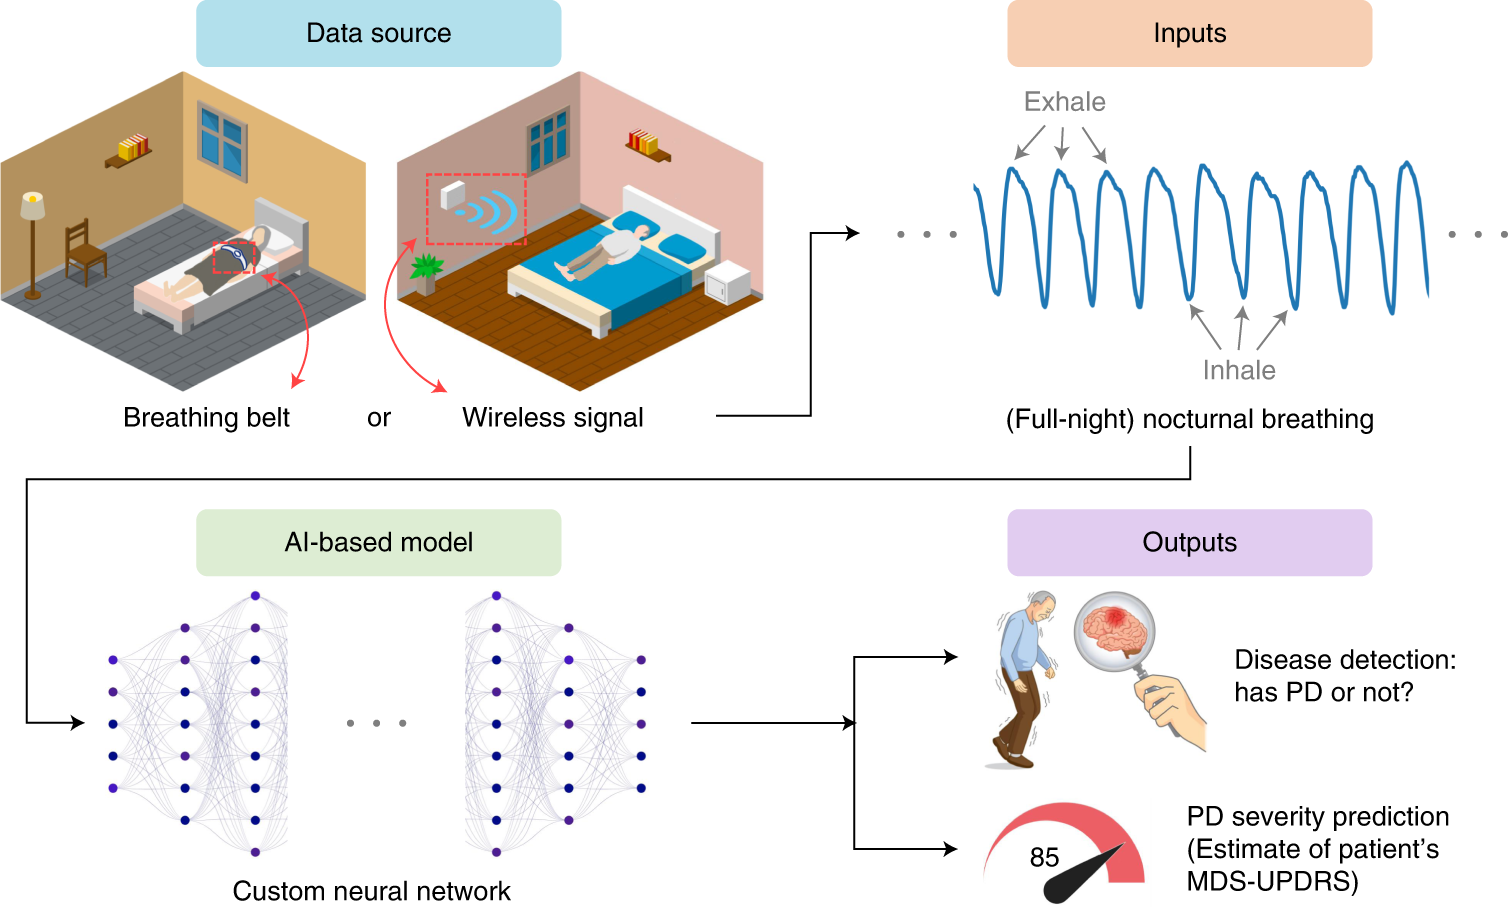

Artificial intelligence-enabled detection and assessment of Parkinson's disease using nocturnal breathing signals